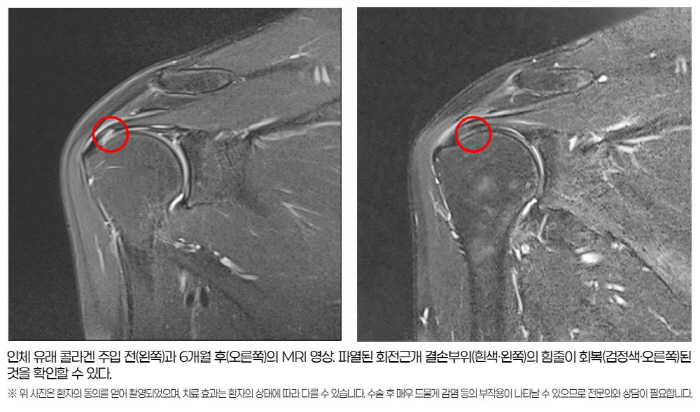

이번 연구의 가장 큰 성과는 MRI를 통해 힘줄의 구조적 회복을 직접 확인했다는 점이다. 6개월 후 MRI 분석 결과, 회전근개 손상 지표인 신호강도의 호전 및 파열 부위의 재생이 1㎜ 이상 나타난 환자가 83.33%(25/30명)에 달했다. 파열 부위가 2㎜ 이상 감소한 환자도 26.66%(8/30명)를 차지했다.

또한 심한 염증을 나타내는 체액저류 현상이 환자의 절반 이상인 53.55%(16/30명)에서 유의미하게 감소했다. 이는 통계적 유의성(p<0.05)을 확보한 결과로, 콜라겐 주입술이 힘줄의 조직 재생을 돕고 손상에 의한 염증을 완화하며 파열의 크기를 줄이는데 효과가 있음을 시사한다.